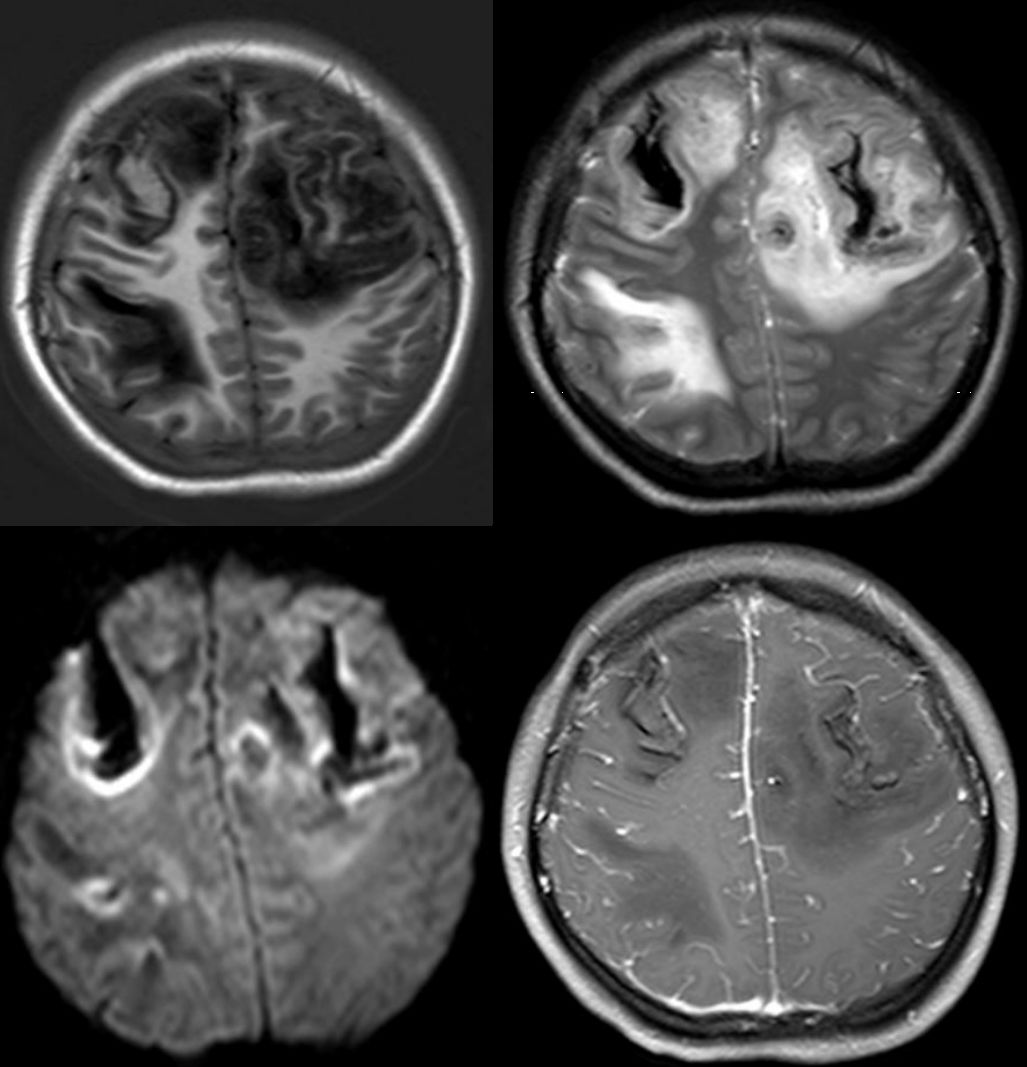

病例13

女性29岁,突发头痛1天伴左下肢麻木无力。头痛呈持续性胀痛,进行性加重,不伴恶心呕吐,无意识障碍等。二便正常。血压120/80mmHg;体温36.8℃。

答案:静脉性脑梗死。

静脉性脑梗死好发生于年轻女性,病程急,于静脉窦血栓形成关系密切,尤以上矢状窦栓塞为著。典型影像表现为上矢状窦引流区单发或多发出血性梗塞,周围脑组织肿胀,增强扫描上矢状窦出现“空三角征”,MRV上常可见到上矢状窦周围侧枝形成。比较遗憾的是本例患者并未行MRV检查,但其发病年龄、临床表现及影像学特征均支持静脉性脑梗死的诊断。